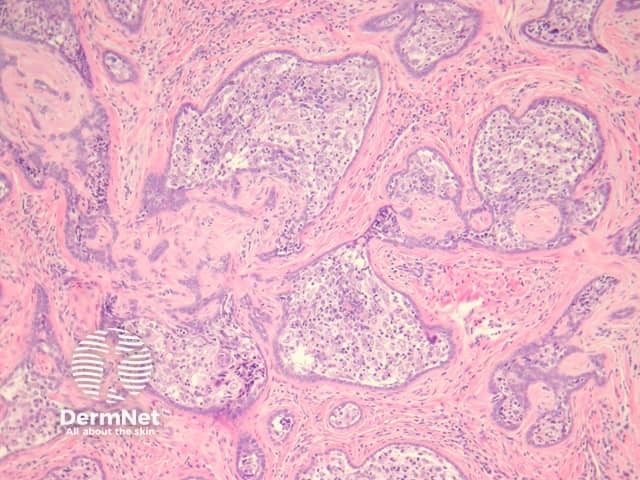

In cutaneous lymphadenoma, there is a well circumscribed dermal mass composed of large tumour islands. The surrounding stroma is fibrotic and is intimately connected to the epithelial islands (figures 1, 2). The islands are infiltrated by impressive populations of lymphocytes (figures 1–3). There is peripheral palisading surrounding the basaloid follicular cells which make up the tumour islands.

Figure 1